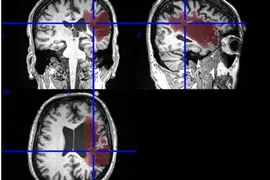

자기공명영상(MRI)으로 알츠하이머 치매의 발생을 예측할 수 있다는 연구결과가 나왔다.

자기공명영상(MRI)으로 알츠하이머 치매의 발생을 예측할 수 있다는 연구결과가 나왔다.

미국 워싱턴대학 의대 말린크로트 영상의학연구소(Malincrockrodt Institute of Radiology)의 Cyrus Raji 박사와 연구팀은 "MRI의 일종으로 대뇌피질의 특성을 측정하는 기법인 확산텐서영상(DTI: Diffusion Tensor Imaging)으로 치매 발생 가능성을 89~95%의 정확도로 예측할 수 있다."고 밝혔다.

DTI로는 뇌의 속 부분인 수질 즉 백질(white matter)의 관(tract)을 따라 물 분자의 움직임을 관찰할 수 있는데 뇌의 전화선이라고 할 수 있는 백질관이 제대로 연결돼 있지 않으면 인지기능에 문제가 발생할 수 있다고 연구진은 밝혔다.

DTI로는 백질의 완전성(integrity)이 어느 정도인지를 평가할 수 있으며 평가는 백질의 물 분자 이동을 나타내는 분획 이방성(FA: fractional anisotropy) 수치로 표시된다.

연구팀은 인지기능이 저하되거나 치매의 전단계인 경도인지장애(MCI: mild cognitive impairment)에서 치매로 이행되고 있는 노인 61명의 DTI 영상을 비교 분석했다.

이들 중 약 절반이 나중에 치매로 이행됐는데 이들은 다른 노인에 비해 FA 수치가 낮았다. 이들은 또 뇌의 특정 전두엽 부위 백질관이 현저히 감소한 것으로 나타났다.

FA 수치와 기타 백질 완전성의 척도를 기준으로 치매 발생 위험도를 평가한 결과 치매 예측의 정확도가 89%로 나타났다.

이 노인 중 40명을 대상으로 백질관을 보다 세밀하게 분석한 결과 치매 예측 정확도는 95%까지 높아졌다.

연구진은 "이번 결과는 MRI로 뇌 백질의 완전성을 측정하면 치매 발생을 예측하고 본격적인 증상이 나타나기 전에 치매 발생을 지연시킬 수 있는 대책을 취할 수 있음을 보여주는 것."이라고 밝혔다.